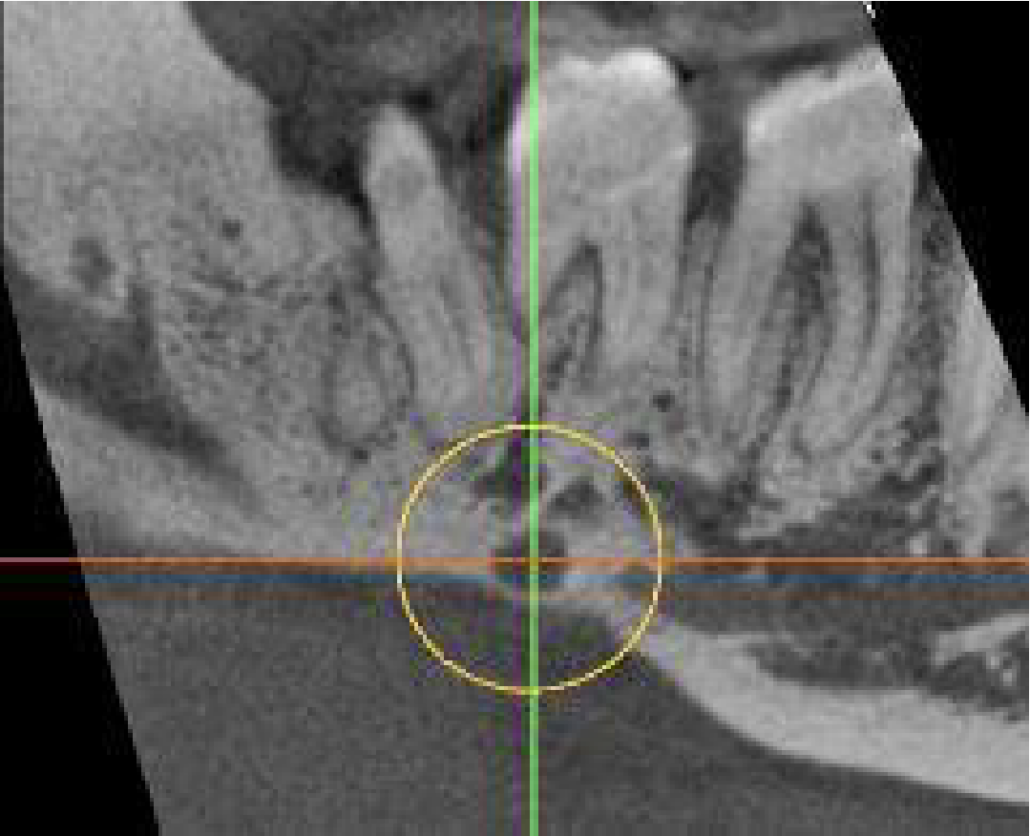

In the lingual cortical plate below the LR7 is a well-defined unilocular radiolucency, 4mm wide with loss of the external surface of the cortical plate and continuous with the bone marrow space. It is very close to the mandibular canal and its inflammation could cause pain.